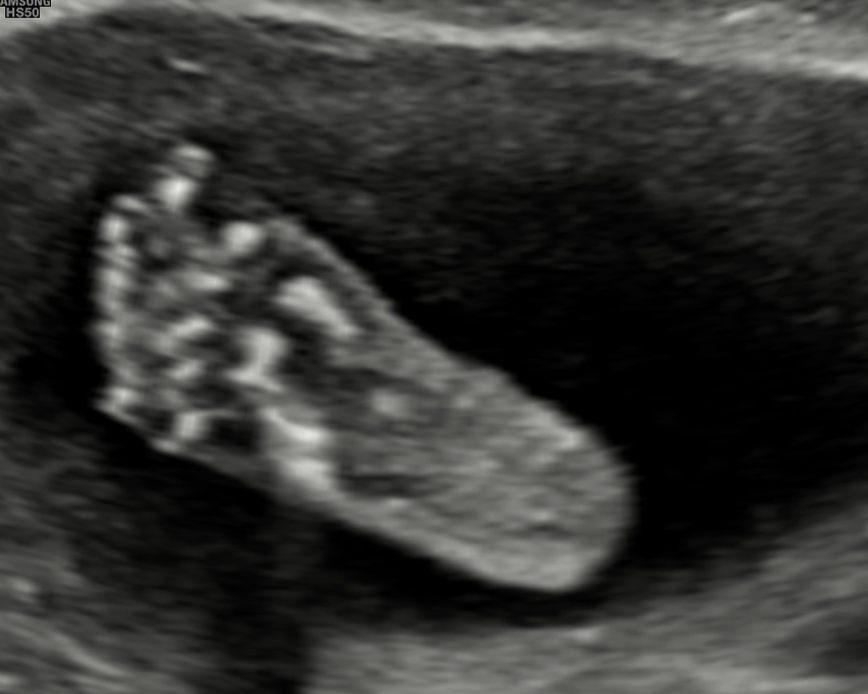

Con nuestra tecnología 5D y 6D de alta resolución, podrás ver la carita, las manos, los pies, la columna y el sexo de tu bebé con imágenes de alta calidad. Además, podrás apreciar los gestos de tu bebé en tiempo real. Esta ecografía también nos ayuda a detectar las malformaciones congénitas que pudiera tener el feto.